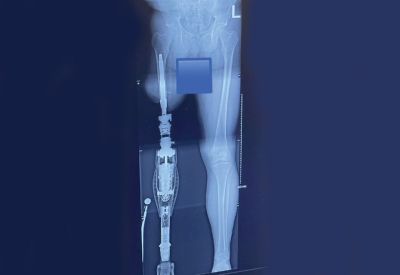

Venezuelan-born Sonia Montanez carries herself with a quiet conviction and the grounded might of someone who has found peace in her own mirror. Her story is one of turning casualties, physical and emotional ones, into a cause to support her now fellow-Canadian amputees.